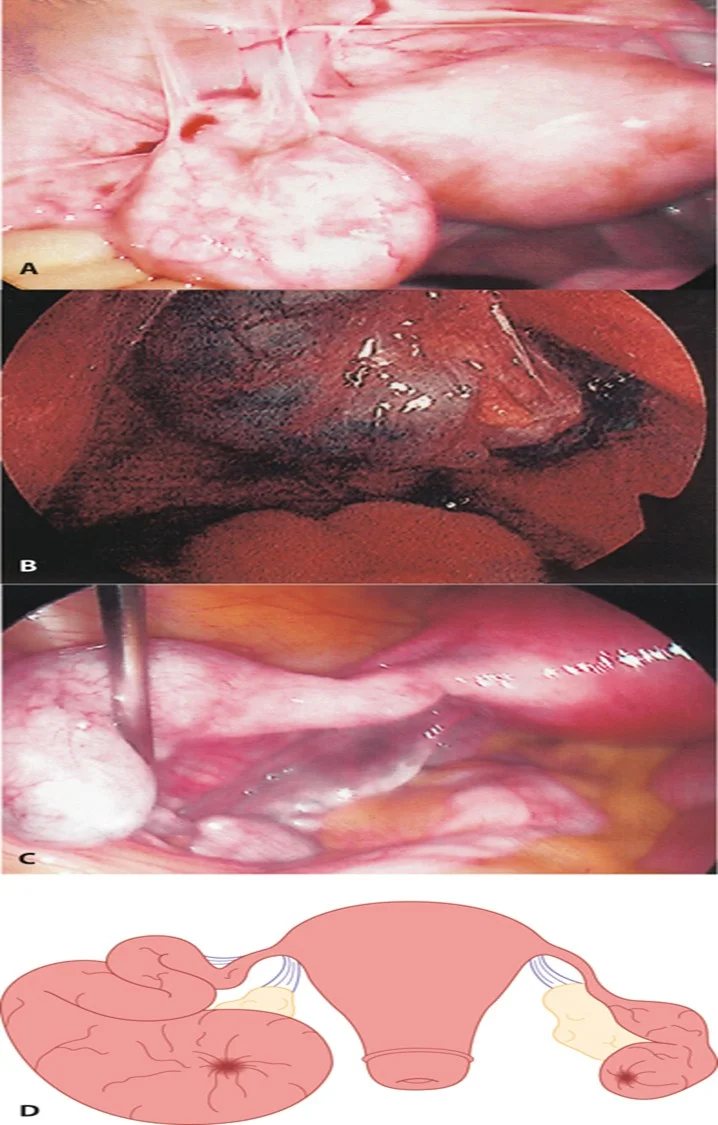

Complications of PID

Fitz-Hugh–Curtis Syndrome

Fitz-Hugh–Curtis syndrome showing perihepatic adhesions (typical violin string appearance).

A Peri-tubal adhesions of the left Fallopian tube; B: Ectopic pregnancy within hydrosalpinx; C: Left Fallopian tube hydrosalpinx; D: Large hydrosalpinx of the left Fallopian tube with a smaller hydrosalpinx on the right side